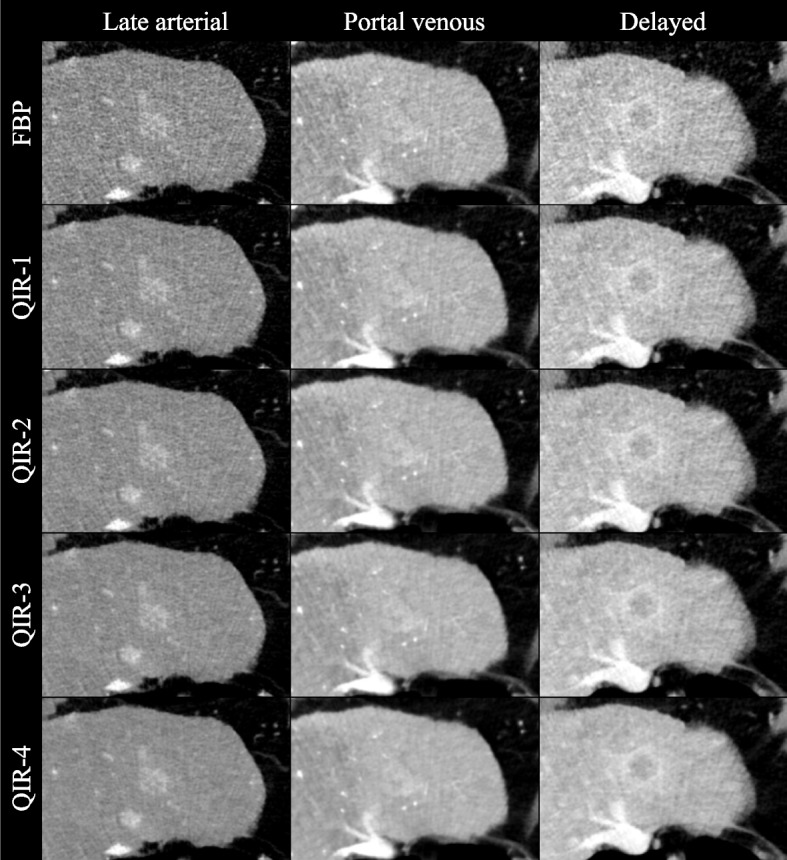

Because high QIR-level images were subjectively assessed as not being relevantly disturbed by blurring effects, improvements in noise, artifacts, and lesion conspicuity consequently resulted in higher overall image quality scores. All differences in the quality criteria reached statistical significance (p < 0.05). A sample series of images illustrating the different QIR levels is shown in Fig. 4.

Fig. 4.

Set of example images. The images of the triple-phase HCC examination protocol reconstructed as filtered back projection and with the available quantum iterative reconstruction levels (QIR-1 to QIR-4). A typical HCC lesion is presented